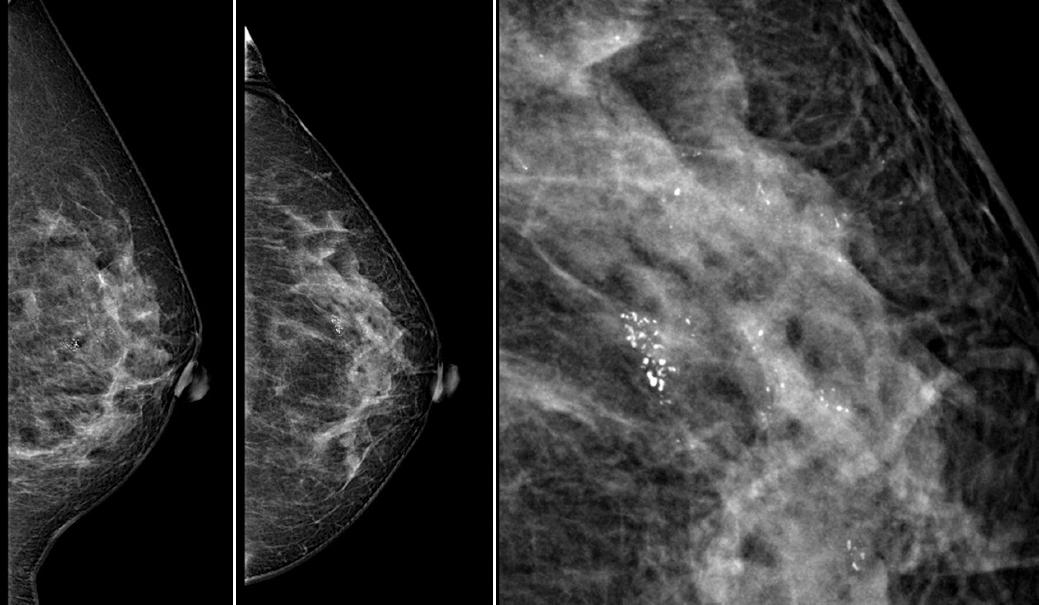

All patients had digital mammography and high-resolution ultrasound. According to the American College of Radiology (ACR) classification, the most frequent breast density was B type with 211 (63.2%) cases, (Table 1). Imaging findings were evaluated. The presence of a nodule or mass detected by imaging studies occurred in 128 (38.3%) of patients, with a clinical median tumor size of 1.5 cm; microcalcifications was present in 276 (82.6%), with a median extension size of 2.7 cm, and one-third of the included population had multicentric disease in radiological studies, the majority of these with a microcalcification focus (Fig. 1). In the biopsy specimen, DCIS grade III was the most frequent histopathological grade in 164 (49.1%) patients (Figs. 2-3). The most frequent surgery was mastectomy in 237 (70.9%) patients.

Figure 1 Digital mammography on left breast with cluster pleomorphic microcalcifications with a biopsy histopathological report of Ductal Carcinoma In Situ (DCIS), with the definitive histopathological study reporting two microinvasion foci within the DCIS.